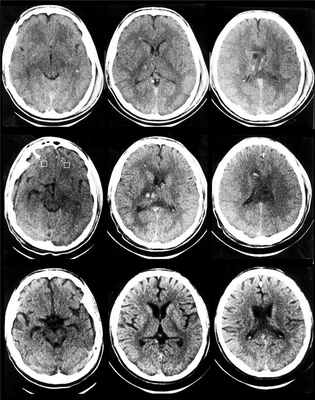

При определенном опыте клинический диагноз ДАП вполне возможен. Однако его всегда следует подкрепить КТ или МРТ. На КТ диффузное аксональное повреждение характеризуется увеличением объема мозга различной степени (вследствие его отека, набухания, гиперемии) со сдавлением боковых и III желудочка, субарахноидальных конвекситальных пространств, а также цистерн основания мозга. При этом часто выявляются мелкоочаговые геморрагии в белом веществе полушарий мозга, мозолистом теле, а также в подкорковых и стволовых структурах (рис. 1).

Вместе с тем еще в остром периоде обнаруживается довольно типичный для ДАП феномен скопления жидкости (с плотностными характеристиками ликвора) над лобными долями, преимущественно в передних отделах с одной или обеих сторон. При легких и среднетяжелых формах ДАП на КТ выявляются лишь признаки незначительного увеличения объема мозга либо компьютерная картина неотличима от нормальной. Повторные КТ-исследования, проведенные у больных с ДАП, обнаруживают довольно характерную динамику. Спустя 2–4 недели после травмы явления отека и набухания мозга регрессируют, мелкоочаговые геморрагии либо не визуализируются, либо становятся гиподенсивными. Вместе с тем начинают отчетливо вырисовываться базальные цистерны и конвекситальные субарахноидальные щели на фоне более или менее выраженной тенденции к расширению желудочковой системы. Вентрикуломегалия и другие признаки диффузного атрофического процесса часто в дальнейшем нарастают (см рис. 1).

КТ картина при диффузно-аксональном повреждении головного мозга (диффузный отек, множество мелких кровоизлияний).